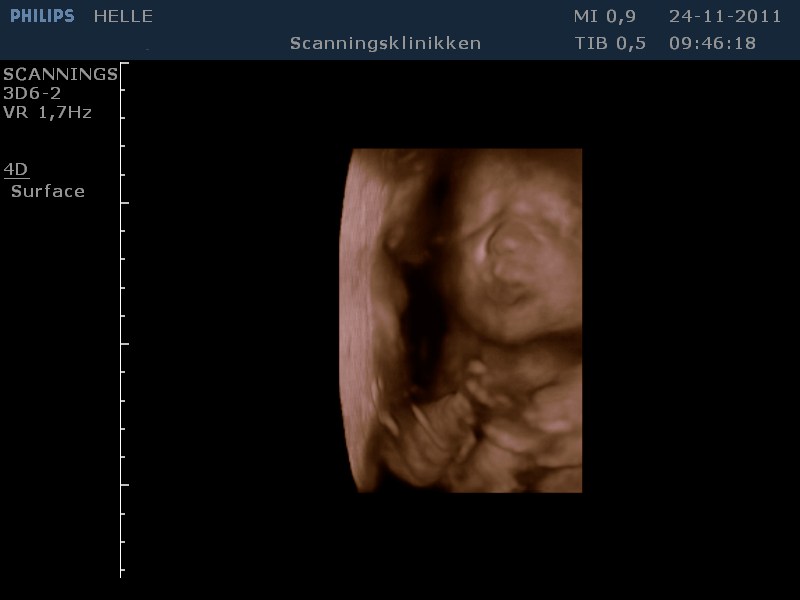

Her går det også godt, - er lige kommet hjem fra en fantastisk 3D scanning. Vores lille pige har det godt og er helt igennem fin! SÅ SØD! Hun har indhentet den manglende vægt og ligger nu lige over gennemsnittet med ca. 1500 g, så det er dejligt!

Jeg er blevet sygemeldt grundet lavt blodtryk, og jeg tror at dette også har haft en positiv indvirkning på hendes vægt. På mandag skal vi til vækstscanning på Hvidovre, - så må vi se om de er enige.

Grundet min stofskifte sygdom, har jeg en del jordmor og læge besøg endnu, men det er jo helt okay, - for jeg har massere af tid, og jeg er jo glad for de holder øje med den lille.